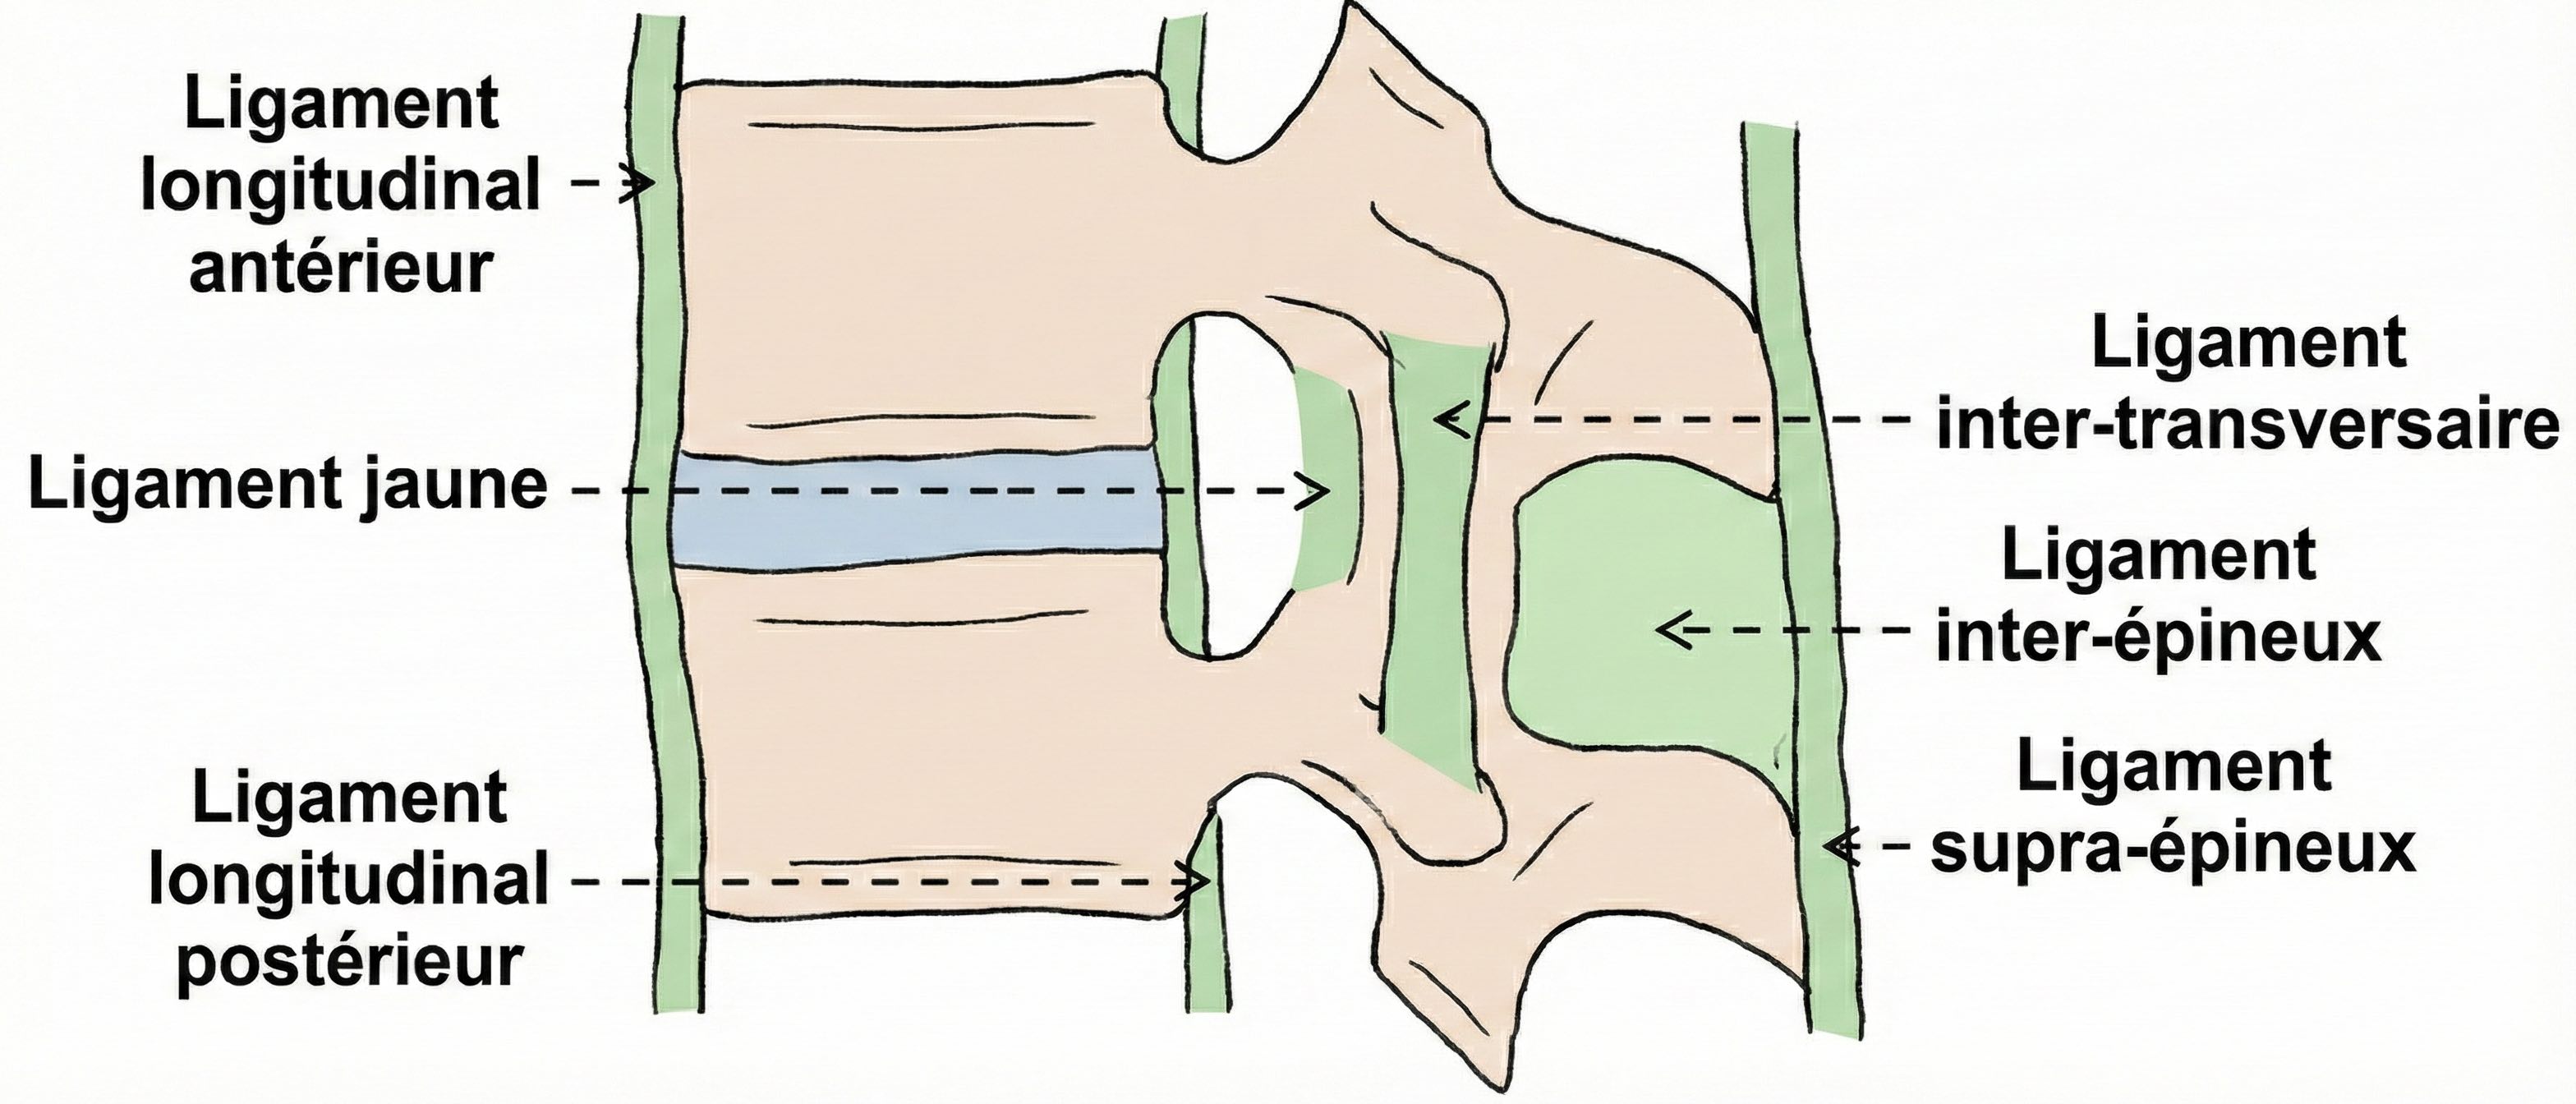

Arthrose zygapophysaire prédominant en sans œdème des berges articulaires.